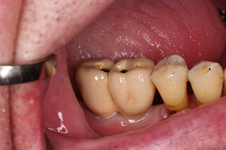

V případě chybění většího počtu zubů v postranních úsecích čelistí je možné ošetření pomocí implantátů, které nahradí ošetření pomocí snímacích náhrad kotvených na zbývajících zubech nebo patře.

Podmínkou je opět dostatečné množství kosti.

Protetické řešení může být pomocí můstku, který je kotvený na implantátech nebo pomocí jednotlivých korunek na implantátech.

V zásadě je možné do těchto můstků zařadit i přirozené zuby, zejména pokud je potřeba tyto zuby ošetřit proteticky

- korunkami. Korunky nebo můstky mohou být na implantáty nacementovány nebo přišroubovány.